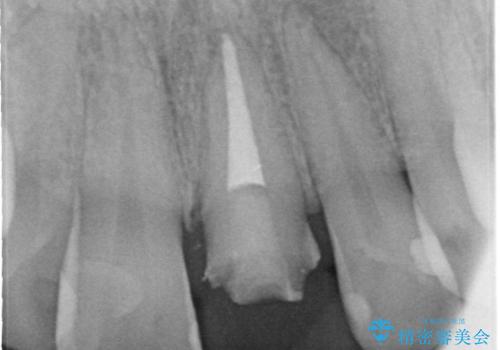

- 左上の前歯の形や色が気になる。

保険の前歯の被せ物のやりかえを希望して来院

- 28.6万円(内訳:根管治療11万円、土台2.2万円、仮歯1.1万円、オールセラミック[スペシャル]14.3万円)費用は治療当時の料金となります

色や形など自然な仕上がりにご満足いただけました。